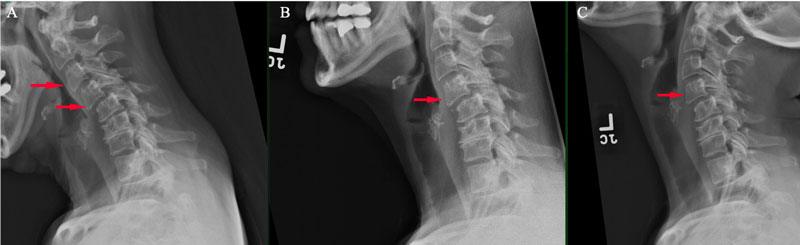

زمانی که پوزیشن یک مهره نسبت به دیگر مهرهها از راستای طبیعی خارج شود اصطلاحاً لیزخوردگی مهره یا اسپوندیلولیستزیس رخ میدهد که باعث بر هم خوردن قوس طبیعی و راستای طبیعی ستون فقرات میشود. بروز این عارضه میتواند بدلیل فشارهای مکرر وارد بر ستون فقرات گردنی مثل پایین انداختن طولانی مدت سر و گردن به سمت پایین، استفاده از بالشت با ارتفاع نامناسب، بلندکردن اجسام سنگین، انجام ورزشها و تمرینهای غیراصولی، وارد شدن ضربه به مهرههای گردنی، بیماریهای استخوانی و ضعف شدید عضلات گردن باشد. در بیمارانی که دچار این عارضه هستند علائمی مانند بی حسی، گزگز، درد در گردن و دستها احساس میشود و همچنین خشکی گردن و تغییرشکل انحنای طبیعی گردن ایجاد میشود.